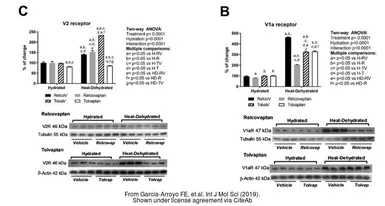

The data was published in the journal Int J Mol Sci in 2019.PMID: 31744099

The data was published in the journal Int J Mol Sci in 2019.PMID: 31744099

The data was published in the journal Int J Mol Sci in 2019.PMID: 31744099

The data was published in the journal Int J Mol Sci in 2019.PMID: 31744099

The data was published in the journal Int J Mol Sci in 2019.PMID: 31744099